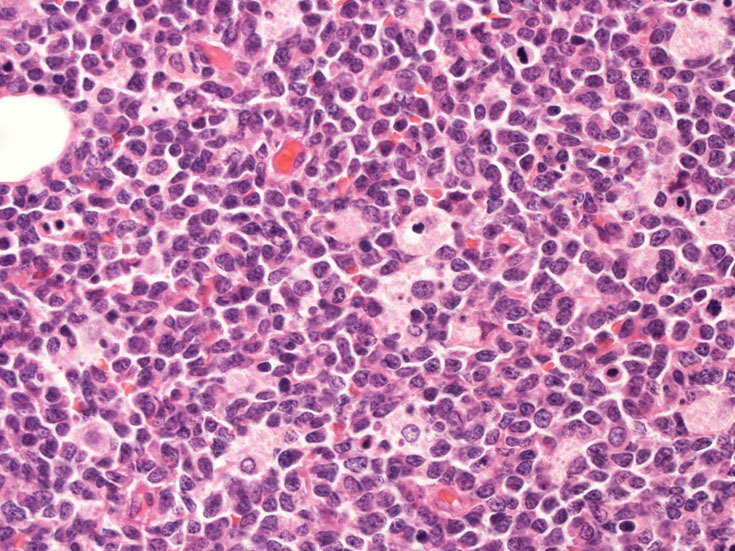

罹患リンパ節の基本構造は消失し腫瘍細胞のびまん性増殖で置換されている。非腫瘍性の小リンパ球(CD3+, CD4/8+)が濾胞様に散在して残る(Fig.01)。不整型または類円形の明るい核をもつmedium-sizeのリンパ球様細胞が密に増殖している。細胞質は乏しい(Fig.02)。CD68陽性macrophageが多く混在する部分が認められた。

Fig03, Fig04は腫瘍細胞の拡大像。大型異型細胞の出現が認められる。腫瘍細胞はCD4+, CD56+, CD123+

この頃はCD4+, CD56+ にCD123陽性で診断が可能であったが, 他疾患でもこの陽性パターンをとることがわかってきた.